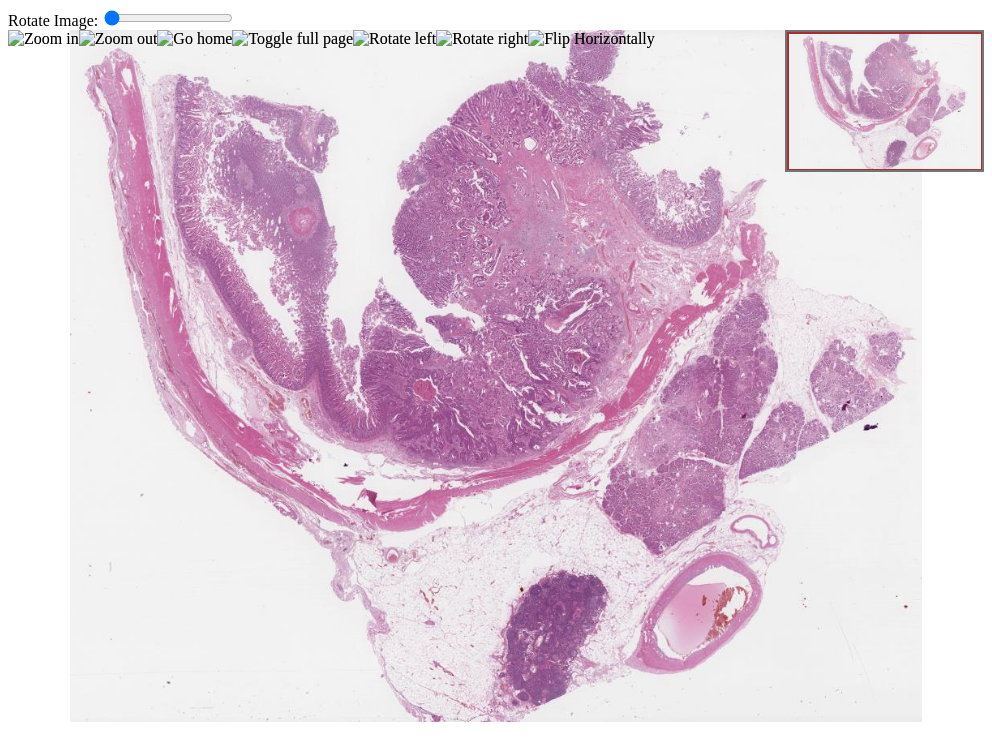

39.1 Adenocarcinoma of Ampulla of Vater

Adenocarcinoma of Ampulla of Vater